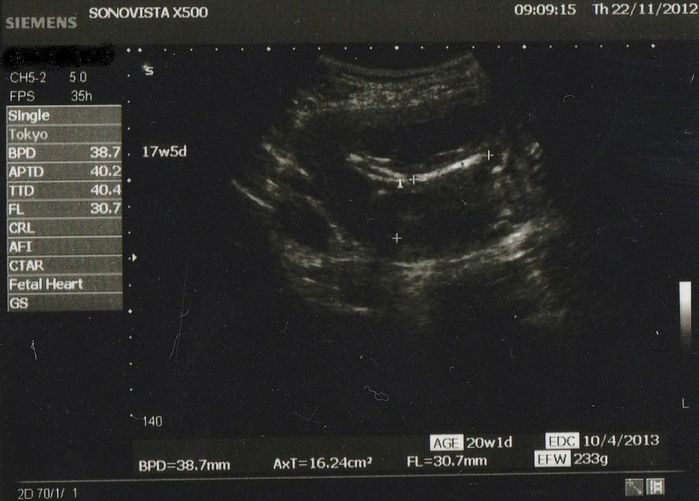

妊娠17週目のエコー写真

約30mmの大腿骨の写真です。推定体重233g! 一度大きくなったおなかだからか、おなかが目立ち始めるのがとっても早く、もう立派な妊婦体型! おなかの写真を撮るときは、長女もちゃっかり自分のおなかをだして一緒に写真を撮っていました。